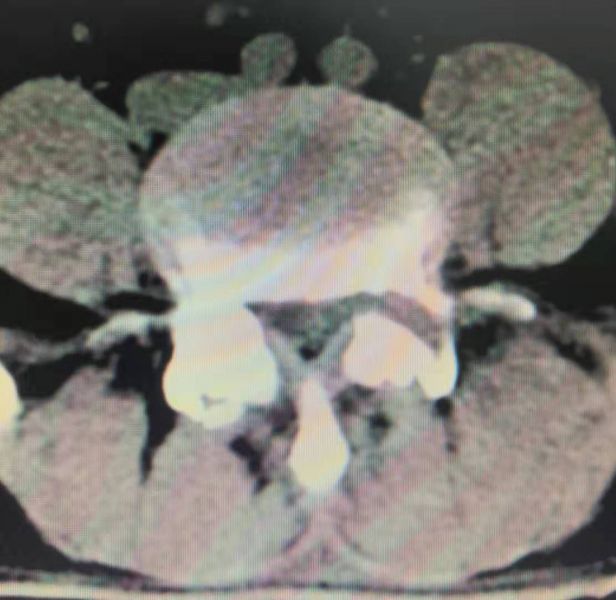

术后脱出椎间盘已摘除

术后打磨的椎弓根骨道

术后椎弓根被打磨一半